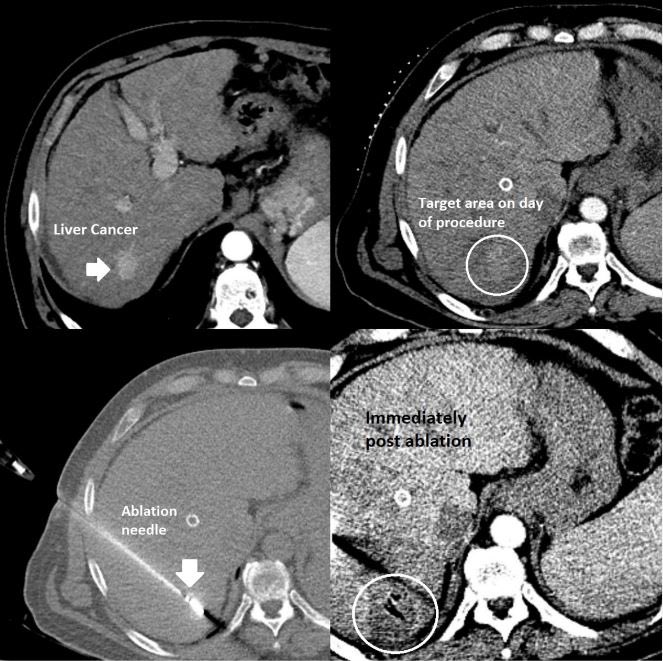

Image-guided ablation by interventional radiology (#IRad), where a thin needle placed through the skin burns the #cancer to death, has similar outcomes to surgery for select patients with liver cancer. This outpatient procedure has fewer complications than #surgery.

Interventional radiology (#IRad) is an important partner in caring for patients with liver disease, from relieving portal hypertension to opening obstructed bile ducts to killing #cancer. This small #cancer was burned to death via a small needle placed under CT guidance.